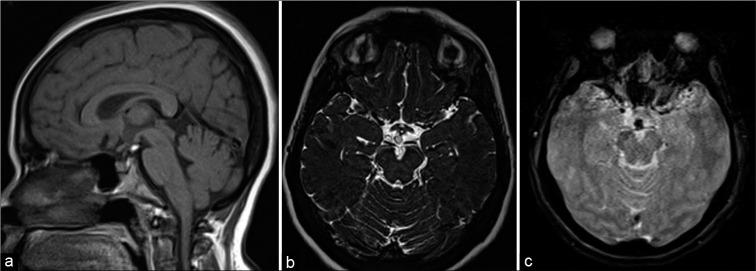

Intracranial lipomas are rare congenital malformations which are present in choroid plexus or subarachnoid locations along the corpus callosum and cisterns. Most of them are identified incidentally during neuroimaging studies done for other indications. Sometimes, they may be associated with other anomalies such as agenesis of corpus callosum and vascular malformations. In magnetic resonance imaging (MRI), they may be associated with chemical shift artifact (CSA) due to their lipid content and can mimic other more serious intracranial lesions. This effect seen in gradient echo MRI sequences can also be used to confirm the presence of these lesions. We report the imaging findings of six patients with intracranial lipomas that showed this chemical shift artifact with a review of the literature.

颅内脂肪瘤是罕见的先天性畸形,存在于脉络丛或沿胼胝体和脑池的蛛网膜下腔位置。它们大多在因其他指征进行的神经影像学检查中偶然发现。有时,它们可能与其他异常有关,如胼胝体发育不全和血管畸形。在磁共振成像(MRI)中,由于其脂质含量,它们可能与化学位移伪影(CSA)相关,并可模仿其他更严重的颅内病变。在梯度回波MRI序列中看到的这种效应也可用于确认这些病变的存在。我们报告了6例显示这种化学位移伪影的颅内脂肪瘤患者的影像学表现,并对文献进行了综述。